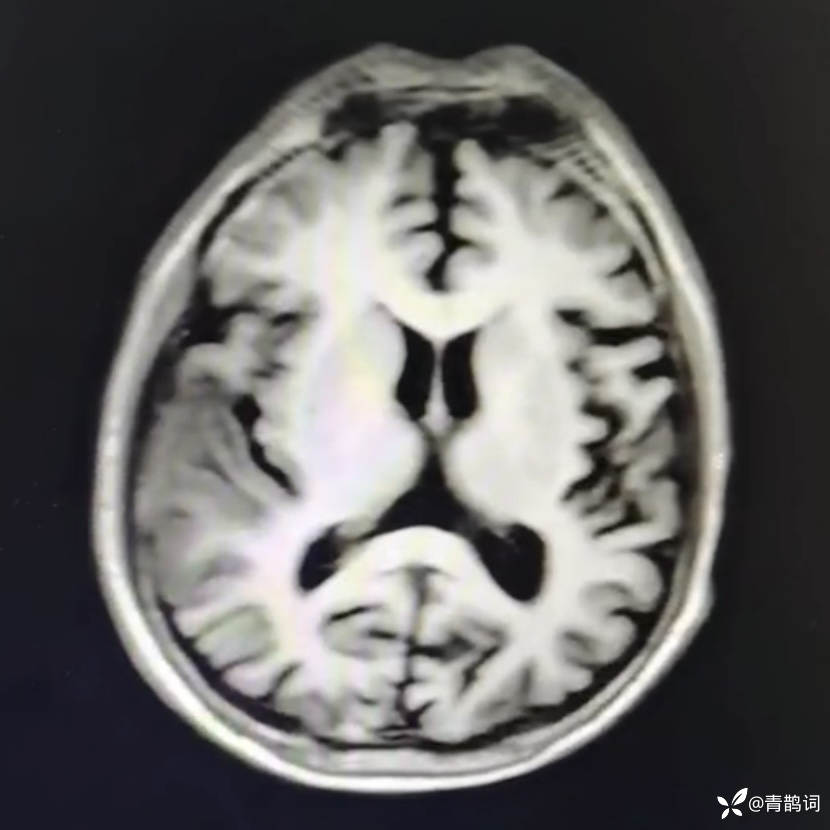

乐痴于医等 2人推荐简要病史:42岁男性,记忆力下降及听力下降一年余。既往体健,否认前驱感染病史。否认家族史。三个月前就诊于当地医院,自述腰穿脑脊液乳酸增高。现就诊于我院,查体记忆力下降,计算力下降,定时定向差,吟诗样语言。完善磁共振如下:

T2: